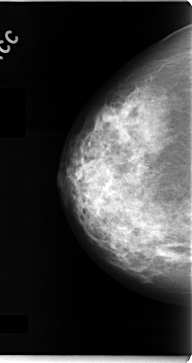

C_0062_1.RIGHT_CC

RIGHT_CC LINES 4712 PIXELS_PER_LINE 2488 BITS_PER_PIXEL 12 RESOLUTION 50 NON_OVERLAY